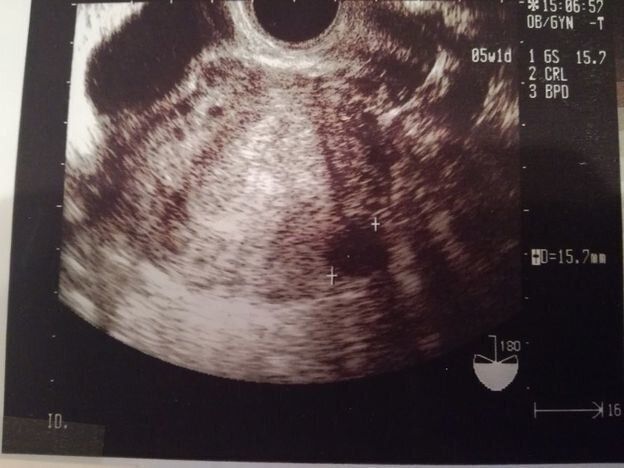

チャーミー小結さんの妊娠5週目のエコー写真

妊娠検査薬で陽性反応が出た翌日、病院を受診して最初に撮ったエコー写真です。この時点で妊娠5週目。初めて見る画像でしたが、モニターに映った瞬間「いる!」と胎芽の入っている胎嚢(袋)が確認できました。